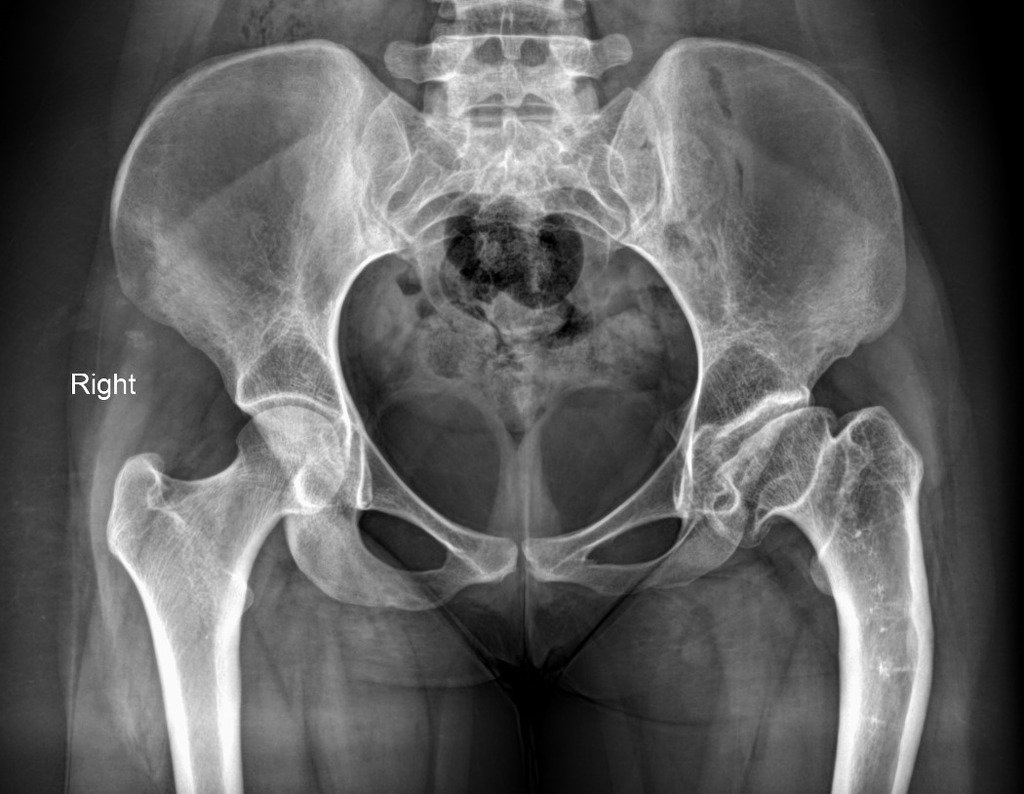

One of the real ball-and-socket joints in the body is the hip joint. The acetabulum, or hip socket, is a deep cup that surrounds the ball of the upper thigh bone. The femur is the thigh bone itself, while the femoral head is the ball on the end. The ball and socket configuration allow for a wide range of motion in the hip, which is necessary for daily tasks like walking, squatting, and climbing stairs. The hip is surrounded by thick buttock and thigh muscles in the rear and front.

When the blood supply to the femoral head is cut off, osteonecrosis of the hip occurs. The bone in the head of the femur dies and progressively collapses if it is not properly nourished. As a result, the articular cartilage that covers the hip bones degrades, resulting in painful arthritis. The bone at the head of the femur progressively dies due to osteonecrosis.

The time it takes for the disease to develop through these phases might range from months to years. It’s critical to detect this condition early since research shows that early treatment leads to better outcomes. Osteonecrosis can develop from a healthy hip (Stage I) to the femoral head collapsing (Stage IV).